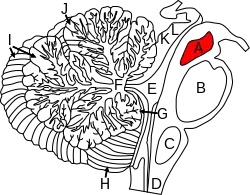

Figure shows the midbrain (A) and surrounding regions; sagittal view of one cerebellar hemisphere. B: Pons. C: Medulla. D: Spinal cord. E: Fourth ventricle. F: Arbor vitae. G: Nodule. H: Tonsil. I: Posterior lobe. J: Anterior lobe. K: Inferior colliculus. L: Superior colliculus. | |